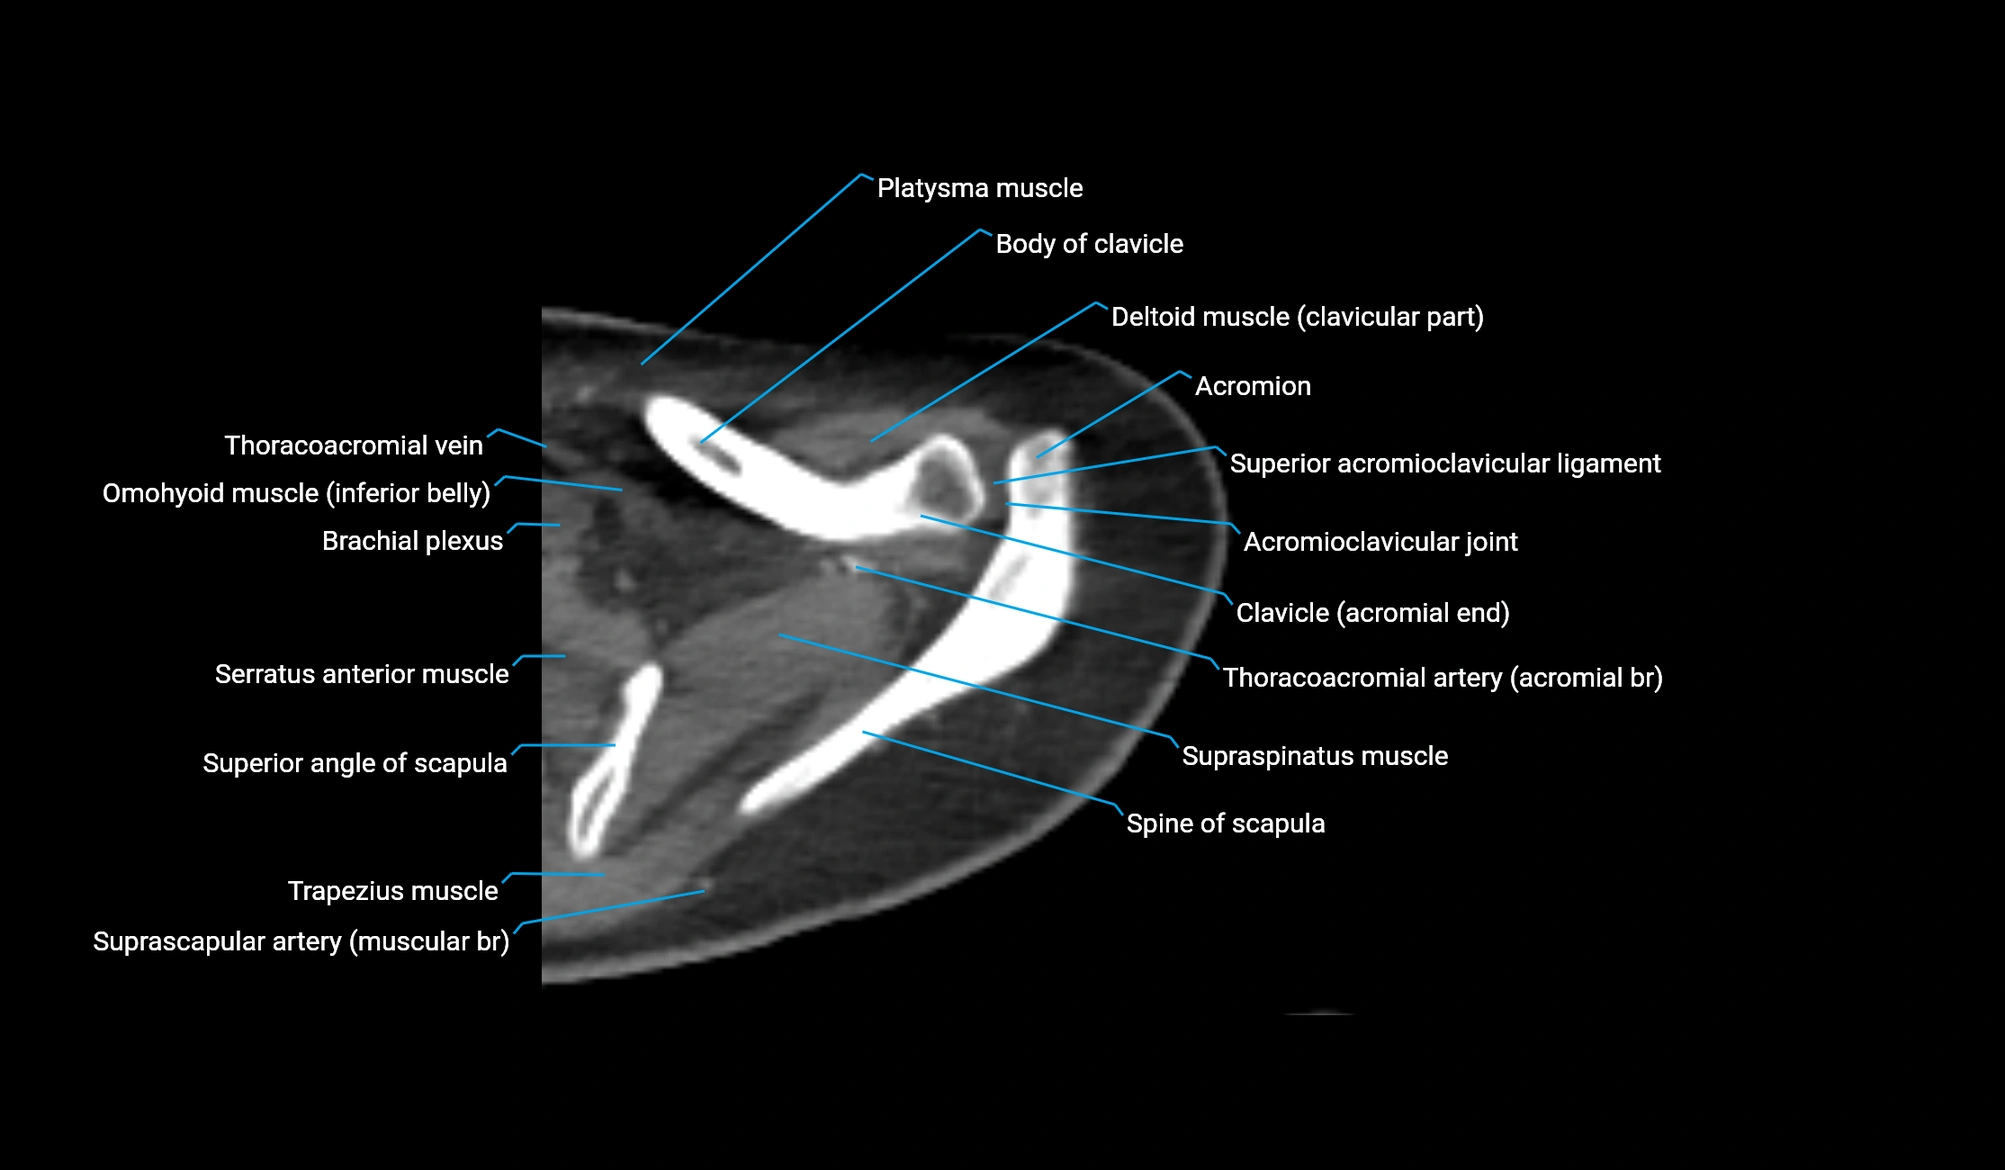

CT image